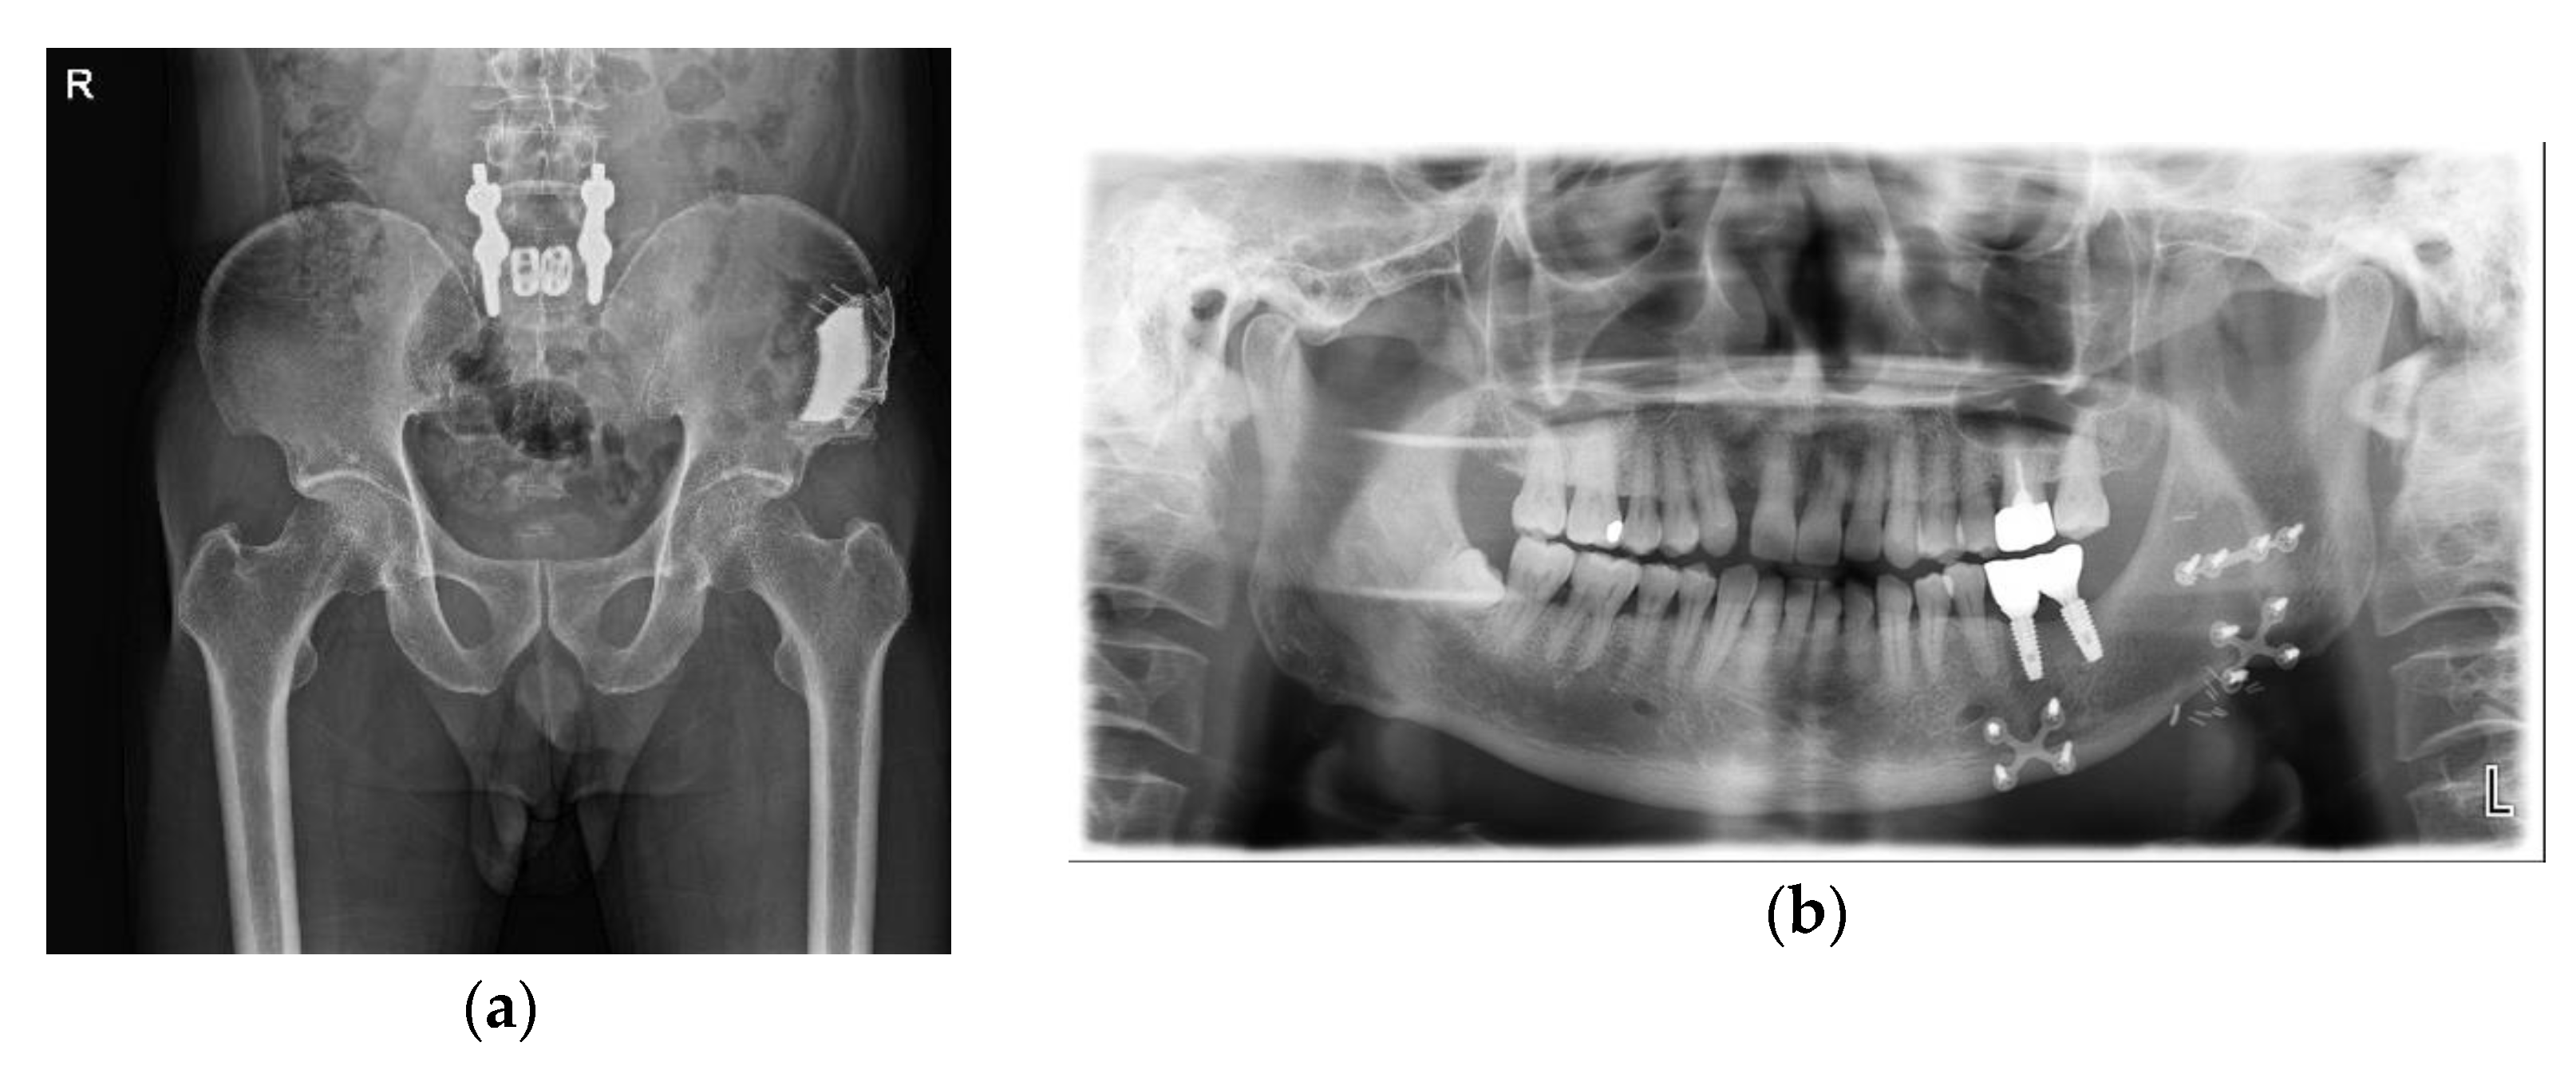

Figure 4.

Postoperative radiograph: (a) patient-specific implant shown on left iliac bone after 3 months; (b) well-reconstructed mandible after 4 months.

Figure 9.

Postoperative radiograph after 1 year: (a) patient-specific implant shown on right iliac bone after 1 year; (b) well-reconstructed mandible and implants were installed 1 year after the operation.